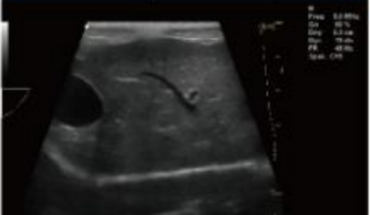

- Equipped with a Wide Range of Probes for Abdominal, Obstetric, Vascular, Cardiac, Small Organ, Urinary Applications

- 3.5 MHz Convex Wide-band Probe

- 6.5MHz Micro Convex Probe